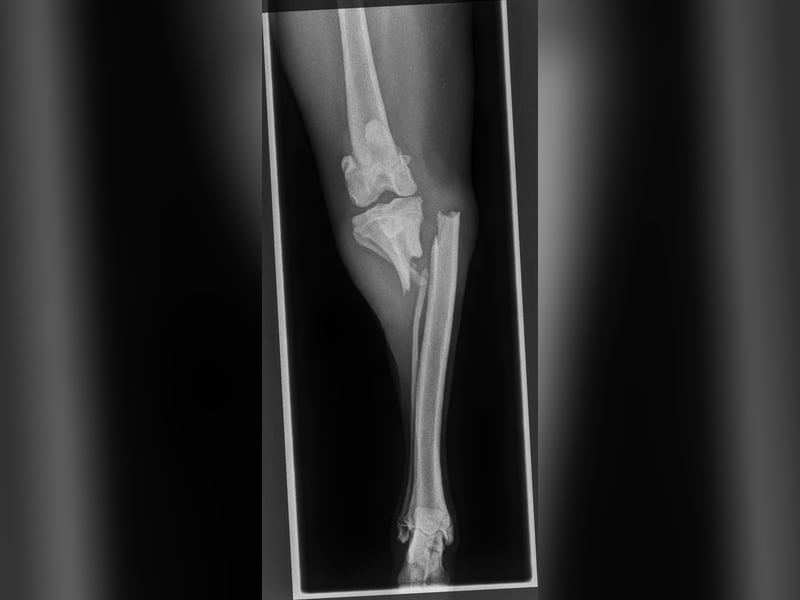

Juno wurde als etwa 7-monatiger Welpe in einem Tierheim auf Kreta abgegeben, in dem wir gerade im Einsatz waren. Zu der Zeit hatte er zwei gelähmte Hintergliedmaßen durch eine Rückenmarksverletzung und einen Knochenbruch am linken Schienbein. Er muss kurz zuvor einen schweren Unfall gehabt haben und hatte zumindest einen kleinen Schutzengel, der ihn uns kurz vor unserer Abfahrt in die Arme leitete.

Durch seinen Unfall und den verwachsenen Knochenbruch hat Juno ein leichtes motorisches Defizit in der Hinterhand behalten, er sollte vorerst nur moderat bewegt werden und braucht dafür hundegerechte Auslastung für's Köpfchen und ganz viel Streicheleinheiten. Als Jagdhund-Mischling ist bei ihm ein Interesse an Wildspuren vorhanden, hierauf muss bei den Spaziergängen und im Training eingegangen werden.